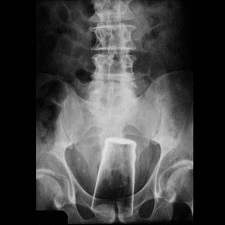

funthing42 ~ Oooh, that would make a such a great bumper sticker! I googled "ass and glass" thinking to find something cutesy and this is what popped up..........don't think it pooped out Shocked

image